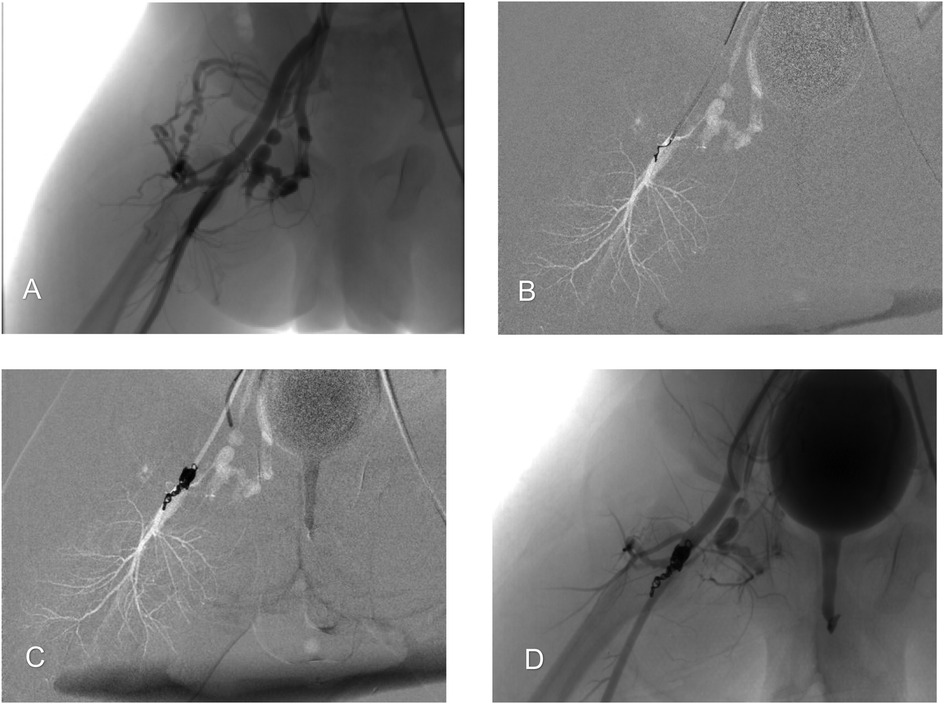

Background: Congenital arteriovenous fistulas (AVFs) are rare, particularly those involving the bilateral femoral arteriovenous system in an infant. This case report details the successful management of this condition using a combined therapeutic approach. Case Presentation: We report the case of a 6-month-old boy who presented with a congenital bilateral femoral arteriovenous fistula, which led to symptoms of fatigue, shortness of breath, and recurrent pneumonia. The patient was successfully treated with a combined therapeutic approach of surgical ligation on the left side and endovascular coil embolization on the right. At the 10-year follow-up, the patient's clinical and echocardiographic status remained normal. The imaging surveillance protocol included regular duplex ultrasound examinations, which confirmed sustained occlusion of both fistulas with no residual dilated veins in the right thigh. The patient remains asymptomatic with no evidence of recurrence. Conclusion: This case highlights the importance of a tailored, combined-modality approach for complex congenital AVFs, especially when the fistulas on each side possess different anatomical characteristics. The specific morphology of the fistula is a critical determinant in choosing the optimal treatment strategy to ensure complete closure and prevent long-term complications such as high-output cardiac failure. This approach serves as a valuable clinical reference for the management of similar complex vascular anomalies in the pediatric population.